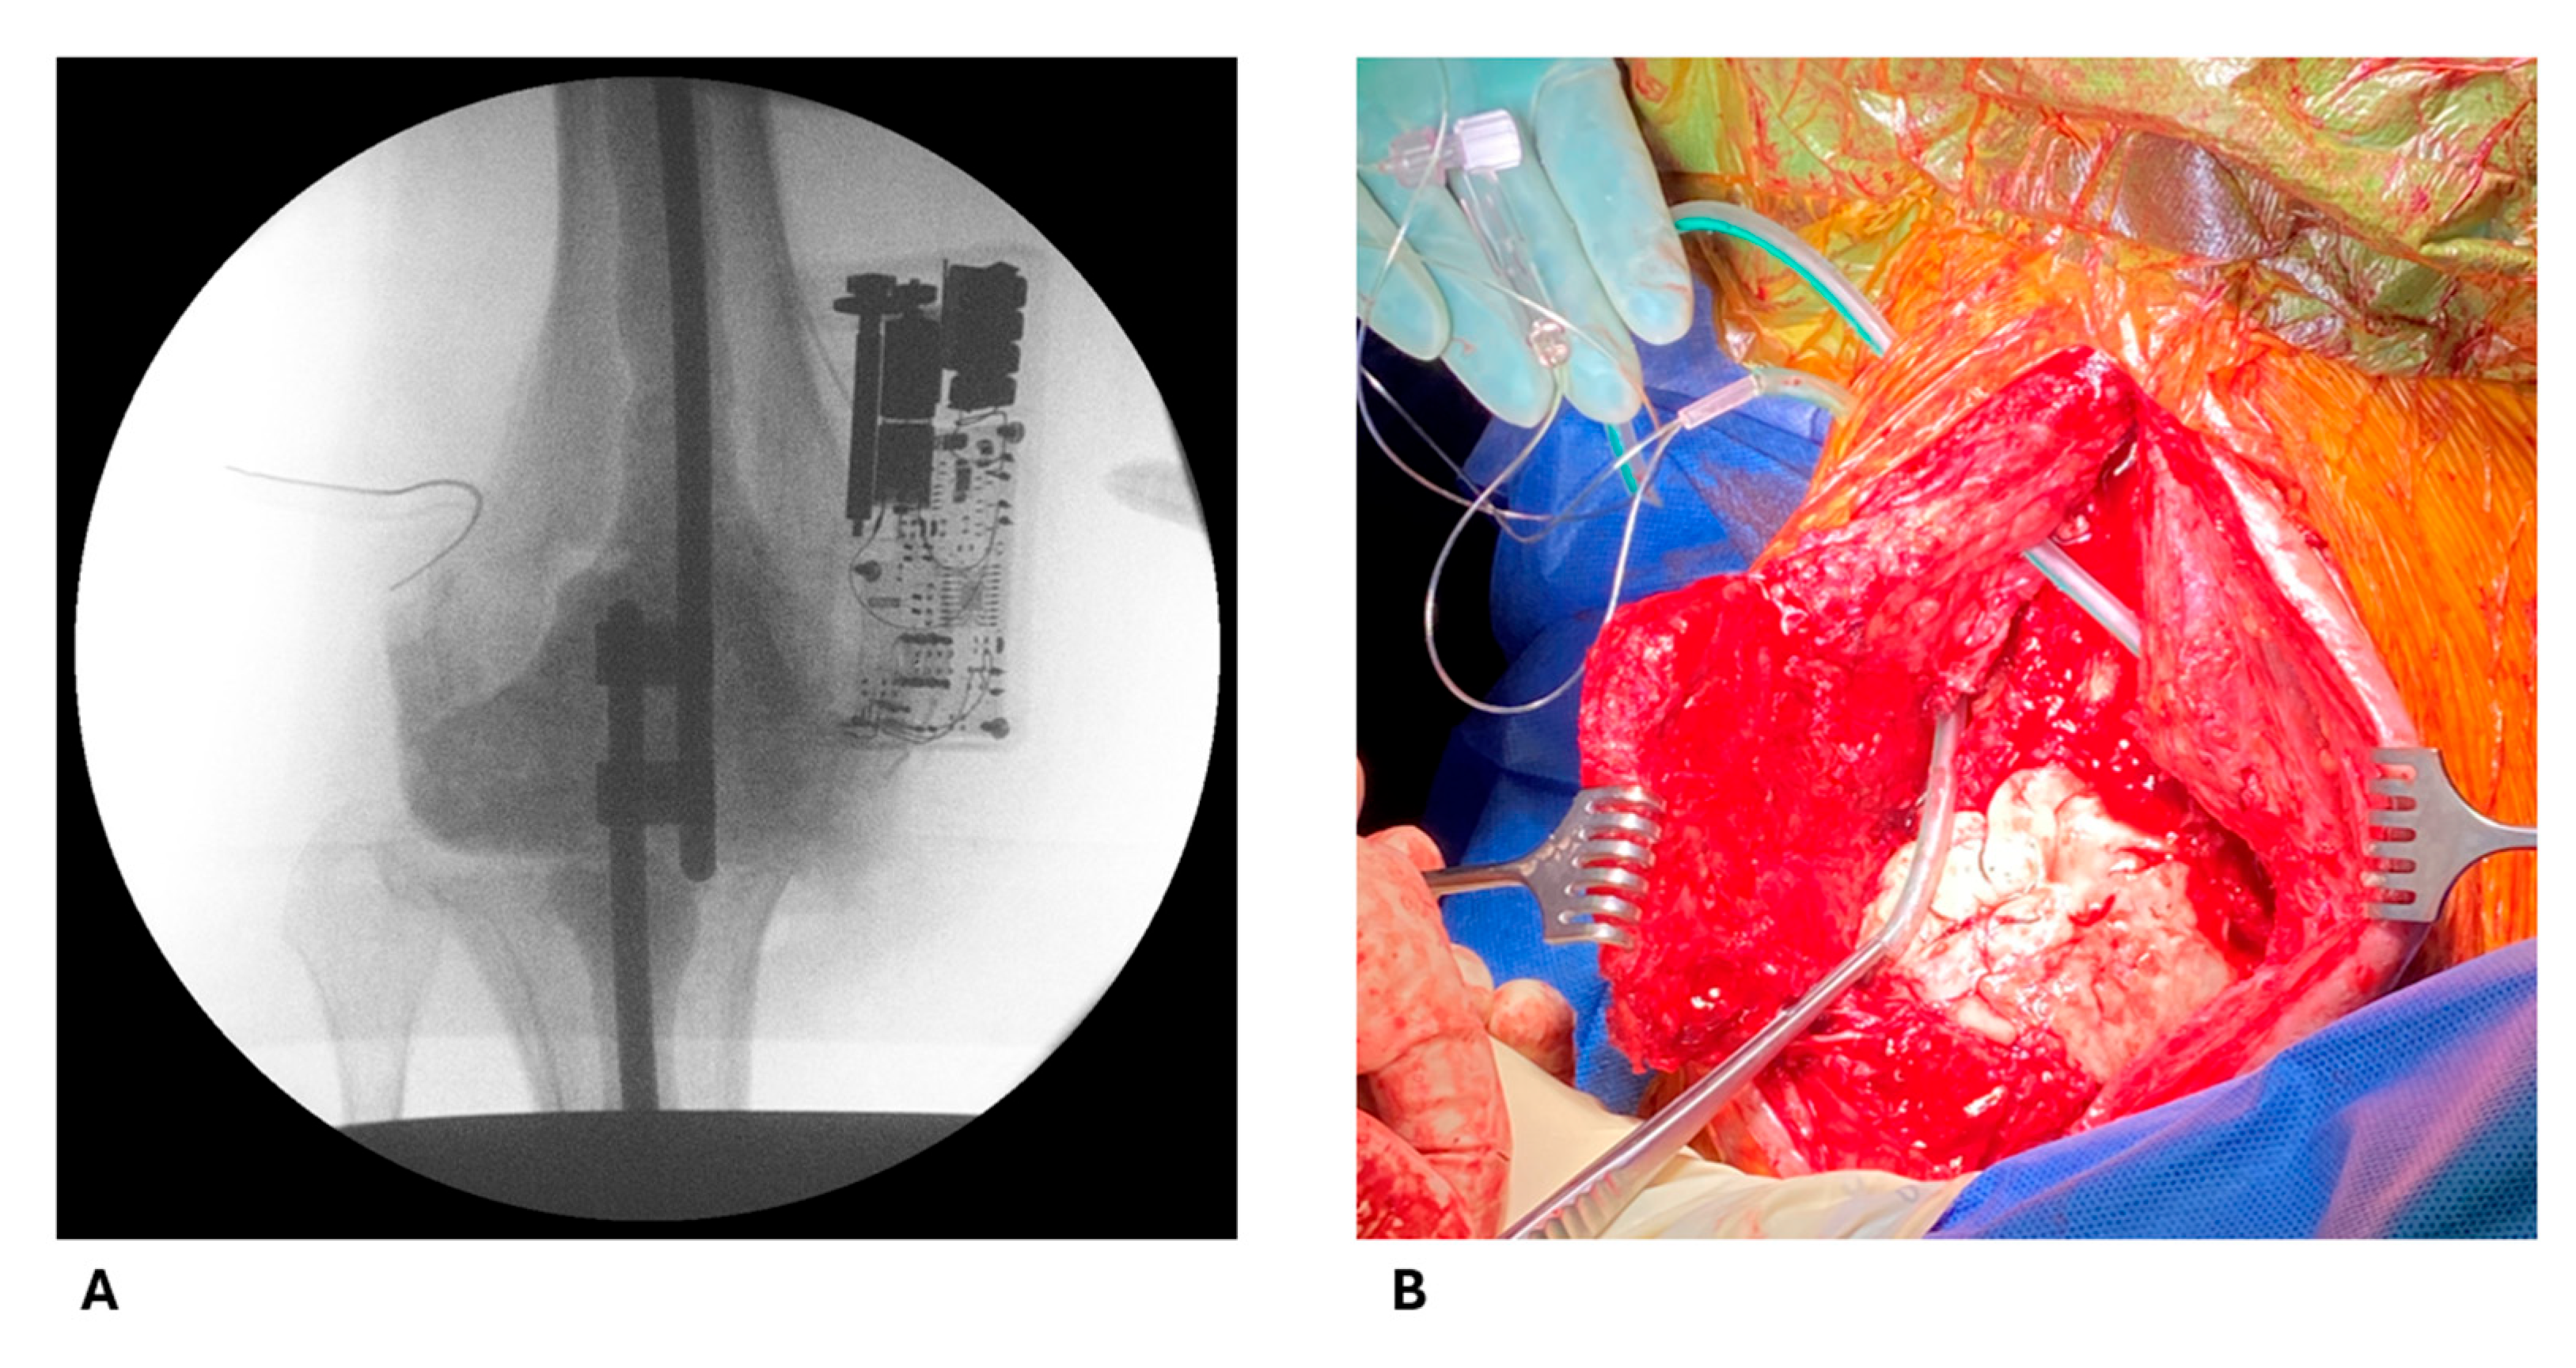

2.1. Antibiotic Concentrations

4.1. Study Design

4.2. Intraoperative Procedures